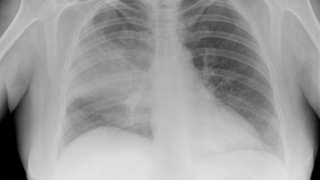

Capnocytophaga canimorsus

Capnocytophaga Gram-stain